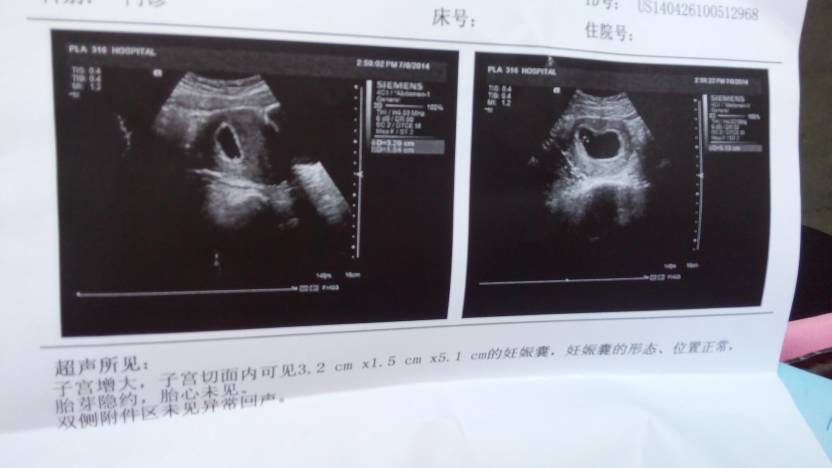

有谁帮我看看这个 有谁帮我看看这个 点击展开 我操了 2014-07-08 15:46 为您推荐: 其他回答 等几天看看,如果两个多月没有胚芽就不正常 好医生救人 2014-07-09 16:53 多久了 好医生救人 2014-07-09 16:48 你好,这个是受孕的表现的,恭喜你,注意休息,可以服用叶酸,如果身体没有异常的三个月后开始到医院产检 好医生救人 2014-07-09 15:53 那你末次月经到现在多久了啊? 小时代↙、大幸福 2014-07-08 16:05 我昨天去查的。54天,有胎心。 小时代↙、大幸福 2014-07-08 15:55 加载更多 相关问题 谁能帮我看看,这是不是有一个多月了啊 谁帮我看看,这个通过吗、健康吗?谢谢 这个报告单有谁会看的 帮我看看